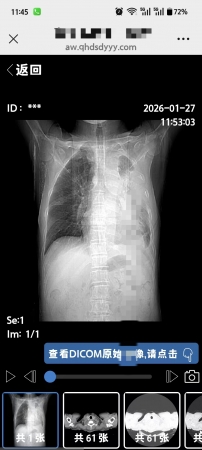

新冠白肺肺不張中藥治療效果 醫(yī)院不治讓出院當(dāng)天片子中藥治療四周的效果,新冠白肺中藥效果還是相當(dāng)?shù)暮?/span>